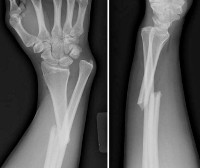

Перелом со смещением. Перелом, при котором отломки утрачивают свое правильное положение и смещаются относительно друг друга. Проявляется деформацией и/или укорочением, реже - удлинением конечности. Существуют различные виды смещения, в том числе - по оси, по длине, ротационное и угловое. Диагноз подтверждают при помощи рентгенографии, при необходимости используют КТ, МРТ, артроскопию и другие исследования. Для устранения смещения проводят одномоментную репозицию, накладывают скелетное вытяжение или применяют различные оперативные методики.

Для постановки диагноза используют данные осмотра и результаты рентгенографии. Обычно назначают снимки в двух проекциях (боковой и прямой). При некоторых переломах со смещением применяют дополнительные проекции (косые, в специальных укладках). Для детального изучения плотных структур назначают КТ кости, для оценки состояния мягких тканей - МРТ. При некоторых внутрисуставных переломах назначают артроскопию. При подозрении на повреждение нервов и сосудов пациентов направляют на консультации к неврологу и сосудистому хирургу.